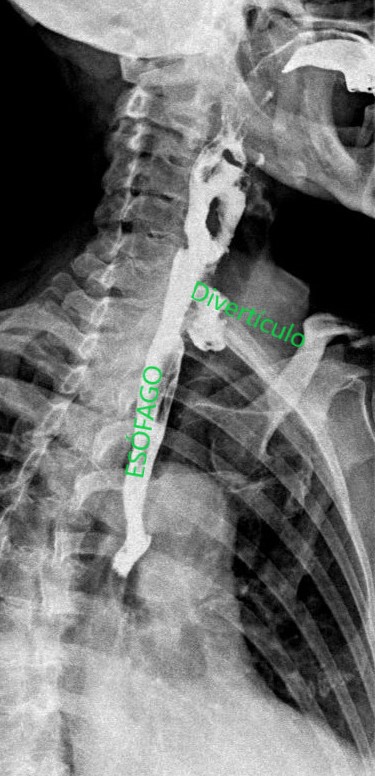

A la paciente se le realizó también un estudio esófago-gastroduodenal (EGD) para su diagnóstico. Se obtuvieron imágenes del esófago mientras que la paciente bebía contraste baritado, observándose el divertículo esofágico (KJ). Comenzamos el estudio en bipedestación (imágenes 6 y 7), después tomaremos imágenes en prono, imagen 8.

Imágenes en OPI en bipedestación donde se observa el paso de contraste por el esófago y una imagen sacular: divertículo esofágico